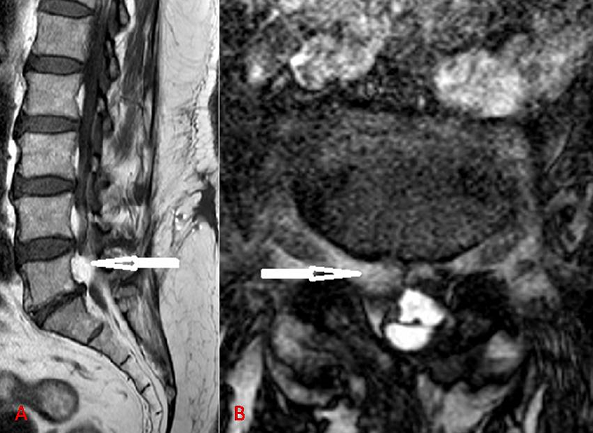

Spinal epidural lipomatosis (SEL) is defined as normal adipose tissue that is pathologically overgrown in the epidural space of the spinal canal. It usually occurs in obese people, patients with history of corticosteroid use or endocrinopathy. They usually present with gradually progressing symptoms and are rarely associated with rapidly aggravated neurologic deficits. Radiologic assessments are mostly conducted by using MRI. A 65-year-old woman presented with isolated low back pain. She had no history of corticosteroid use, endocrinopathy or radicular pain. On examination, she was obese (height 155cm, weight 87kg) with a body mass index (BMI) of 56.1 kg/m2. Neurological exam was normal with no motor weakness and sensation was intact. Plain radiographs showed no evidence of abnormality, including instability and other pathologic findings. Magnetic resonance imaging (MRI) revealed an epidural mass posterior to the L5 vertebral body that was isosignal to subcutaneous fat and it compressed asymmetrically on the right side of the cauda equina and the exiting right L5 nerve root on sagittal (A) and axial (B) T2 weighted images. There was no evidence of spinal stenosis. The result of electromyography was normal. We recommended surgical intervention to relieve pain but the patient declined. Opioid analgesia has been prescribed and her symptoms became much improved. Weight reduction by physiotherapy and exercise resulted in complete loss of lumbar pain (the patient lost 30kg in 6 months) and MRI control showed a complete disappearance of the mass.